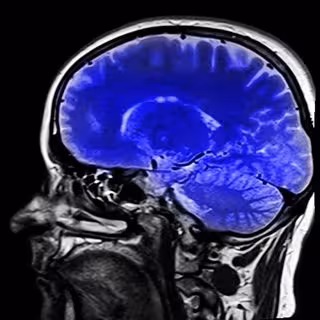

Resonancias magnéticas revelan anormalidades en las estructuras cerebrales de personas con autismo

Resonancia magnética del cerebro

Investigadores estadounidenses han detectado, a través de resonancias magnéticas, anormalidades en las estructuras cerebrales de las personas que padecen autismo que daban lugar a deficiencias cognitivas y conductuales.